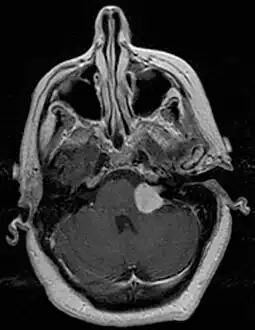

Preliminary diagnostic procedures include ear examination, hearing and vestibular testing. The auditory brainstem response test (ABR) is a cost-effective test to see if a VS has perhaps compromised the cochlear nerve. A computed tomography test (CT scan) will show the presence of a VS, although very small tumors may be missed. The 'gold standard' for diagnosis of VS is magnetic resonance imaging, MRI. The NIH consensus statement for VS in 1991 stated: "MRI now is regarded as the most definitive study that can be performed, and is capable of revealing vestibular tumors as small as a few millimeters in diameter."[10] This remarkable technology superseded the CT scan that was in wide use by 1971 despite its ionizing radiation risks. By using thin-slice sectioning and gadolinium dye contrast, MRI scanners can find even the smallest of tumors without the risk of radiation. This is especially important for spotting rare cases of bilateral VSs where one of the tumors is often only a few millimeters in diameter. Spotting previously missed small tumors meant that the average tumor size at diagnosis decreased.

Unilateral vestibular schwannoma -

Bilateral schwannomas in a person with neurofibromatosis 2